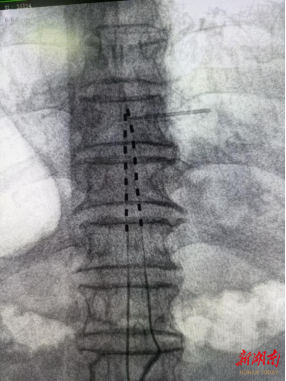

2025年11月,岳阳市人民医院疼痛科李勇辉团队成功为一名饱受顽固性腰腿痛折磨的患者实施脊髓电刺激器(SCS)永久植入术。该技术填补了岳阳地区治疗持续性脊柱术后疼痛综合征神经调控治疗的空白,标志着岳阳在持续性脊柱术后疼痛综合征领域进入神经调控精准微创治疗新时代。

经过详尽的术前准备,并向龙嗲详细解释手术原理,李勇辉团队随即为患者安排了一期微创手术,术后即刻返回病房,为龙嗲开机测试,并调整参数,疼痛区域被温和酥麻感替代,NRS评分降至2-3分。

一期测试:手术微创,费用较低,在DSA引导下电极植入,7天刺激器外挂测试,疼痛缓解>70%;

二期永久植入:火柴盒大小脉冲发生器埋入腹部皮下,终身程控调节。